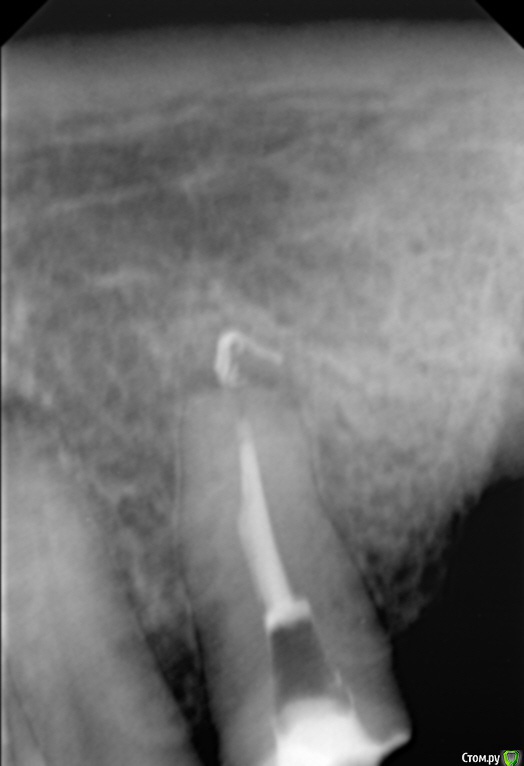

Елена509 Опубликовано 19 ноября, 2015 Поделиться Опубликовано 19 ноября, 2015 Доктора, помогите, пжл, ситуация какая - ортопед направил для удаления штифта и перепломбирования к.к 35, начали - анестезия, выудили штифт, начали расширять, уперлись на 15 мм, пошли на снимок с гутт штифтом(прилагается), недолет, вернулись, сразу прошли дальше, по апексу -18мм, убавила до 17,5, мастер штифт - 35, латералка, пошли на контроль, а там - загнутый штифт за верхушкой(рг прилагается), вернулись, все вытащила, загнутый тоже(95% - я его прям признала), отмыли просушили, по апексу те же 18мм, примеряю мастер штифты все как то не так встает, в итоге 70 подогнала, на те же 17,5 мм, поставила, с латералкой, идем на контроль, там вот такая вот фигня(рг - "последний"), вопросы - это что, невытащеннный гут.штифт или на его место эпоксидка затекла? что с прогнозом и что делать? 1 Ссылка на комментарий

Сева северный Опубликовано 19 ноября, 2015 Поделиться Опубликовано 19 ноября, 2015 (изменено) перед тем, как пошли делать с гут.штифтом рг недолет показывал, вроде нормально все было, когда пломбировали, штифты тоже никуда не уходили на месте стояли, я даже как то растерялась сильно, когда на контрольном на столько за апекс ушлисудя по фото....зуб резарцинен..... с дефектом твердых тканей( это диазноз)..ферол наверное отсутствует. Чтобы было понятно ......лечение резарциненого зуба с таким разрушением..+ осложненным необходимостью эндолечения .... является альтернативой удалению.Что касается :Что за верхушкой ?.... Границы четкие, если вынули гуту ....крючком.... для себя считайте силер..даже если и гута связь с каналом зуба отсутствует. поэтому реакция будет либо незначительная , либо отсутствовать вообще. Прогноз по зубу, строил бы из ортопедической целесообразности.... Изменено 19 ноября, 2015 пользователем Сева северный 1 Ссылка на комментарий

Л Ю С Я Опубликовано 20 ноября, 2015 Поделиться Опубликовано 20 ноября, 2015 Здесь явная резорбция апекса, поэтому локатор мог показывать неправильно. В таких случаях делайте снимок с финишным файлом, где он? Ориентируйтесь больше на рентгенологическую длину, после лечения может произойти ещё небольшая убыль апекса, поэтому пакуйте -0,5, лучше мта. Какой билдап планируется в зубе? И вообще надо рассматривать картину восстановления окклюзии в целом 1 Ссылка на комментарий

Сева северный Опубликовано 20 ноября, 2015 Поделиться Опубликовано 20 ноября, 2015 лечение таких зубов лучше начинать с диагностического КТ ... Согласен ... с колегой , что здесь возможна резорбция ... но поставить ее можно только по серии ваших снимков. Первый снимок не давал четкой картины.А теперь подумайте как вы поступили , зная это перед лечением. Ссылка на комментарий

Sampson Опубликовано 21 ноября, 2015 Поделиться Опубликовано 21 ноября, 2015 Резорциненный+пародонтитный+ изменения апекальной трети корня+ тень материала за верхушкой = Я бы зуб пока сохранил в целях наблюдения. и раз в неделю проводил перкуссию. При положительной динамике отправил к ортопеду. При отрицательной к хирургу. Ссылка на комментарий